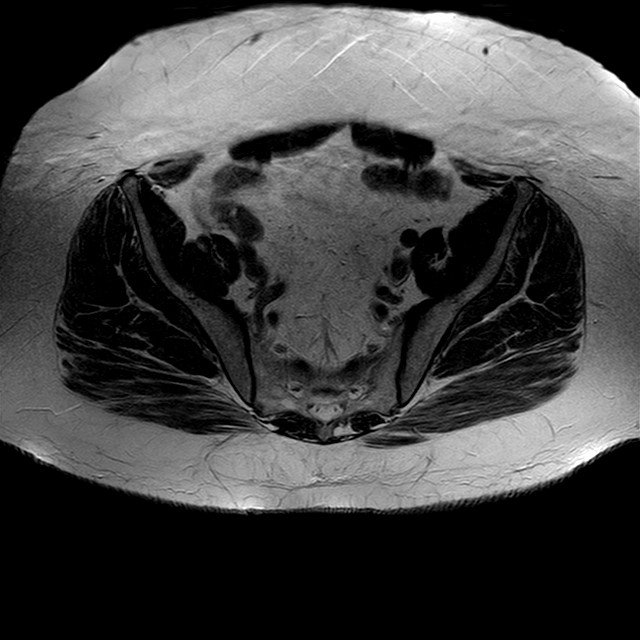

Esami: RMN BACINO

eT2w TSE

Evidenti e simmetriche alterazioni osteofitosiche in regione coxo femorale con riduzione delle rime articolari. Degenerazione completa del cercine glenoideo. Non attuali segni di versamento articolare. Non segni di edema osseo che escludono attuale algodistrofia od osteonecrosi. Lieve e simmetrica riduzione del trofismo della muscolatura glutea.